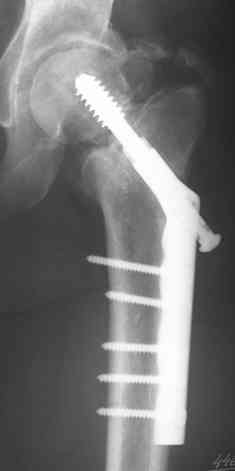

Пациентка 39 лет в декабре 2007г. в результате ДТП получила

оскольчатый метафизарный, Т-образный полный перелом мыщелков правого

бедра, базальный перелом шейки левого бедра. Перелом правого бедра лечили

аппаратом Илизарова, перелом шейки левого бедра синтезировали DHS.

появляющиеся при нагрузке. На контрольных Р-граммах имеется ложный

сустав шейки бедра, прорезывание головки относительно динамического

винта.